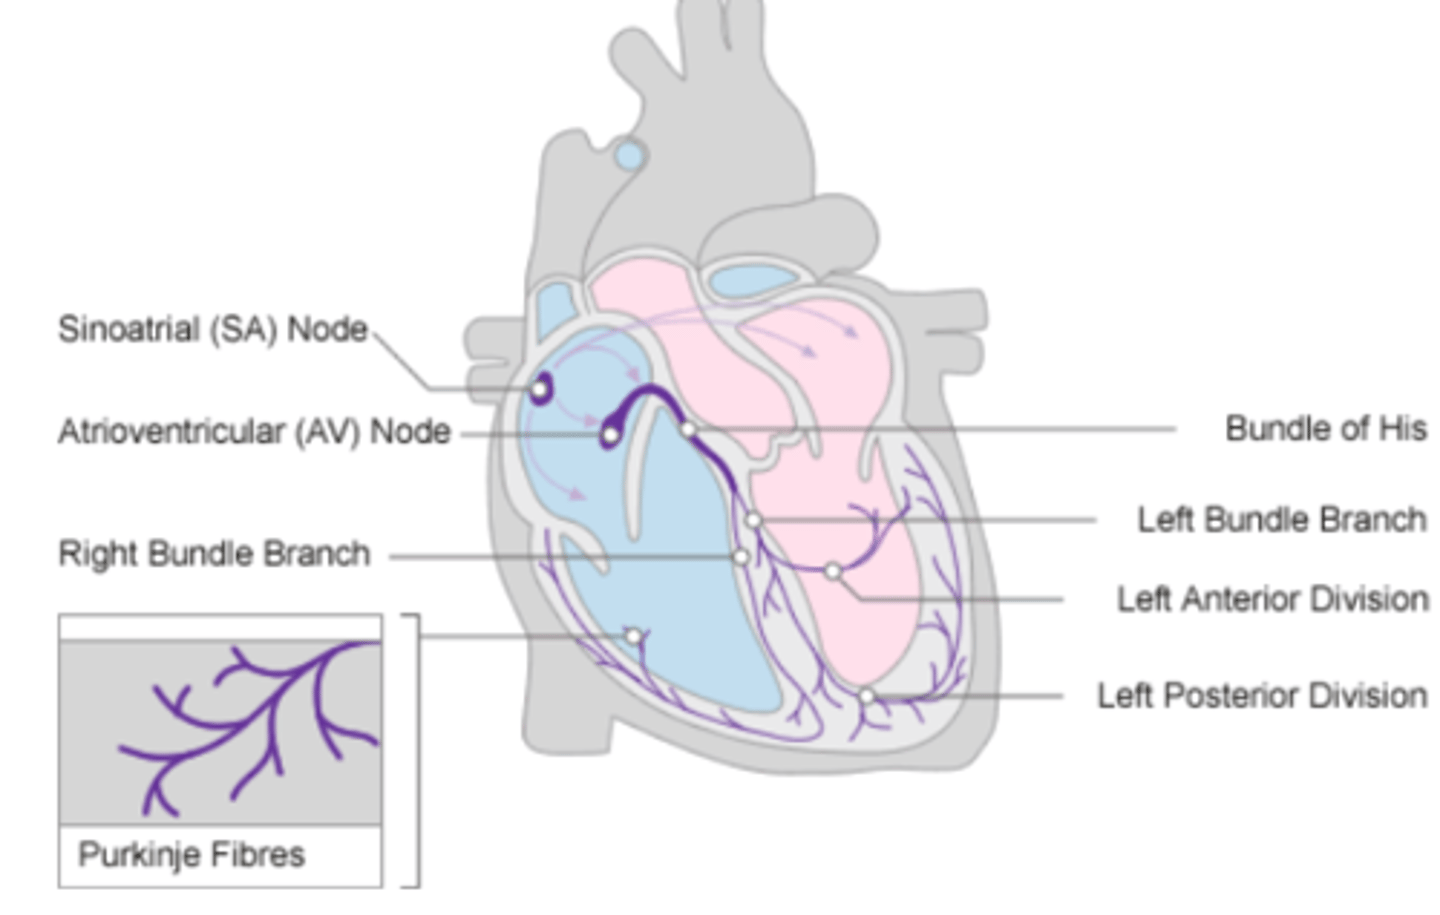

What allows the heart to contract by itself?

The heart possesses a specialized conduction system that gives it the autonomous capacity to contract, allowing it to pump by itself in a correct buffer.

What are the two conduction nodes of the heart conduction system?

. SA node (sinoatrial node)

. AV node (atrioventicular node)

What is the function of the sinoatrial (SA) node?

Where is initiated the contraction of the SA node?

SVC (Superior Vena Cava)

passing through the atrium to the AV node

Where is the SA located?

upper wall of the right atrium,

at the junction where the superior vena cava enters

Where is the atrioventricular (AV) node located, and what follows it?

At the level of the atrioventricular septum,

AV node is followed by?

Bundle of Hiss that divides into two branches

Where does Bundle of Hiss ends?

Purkninje fibers

Describe the propagation of waves in the conduction system ?

. SA node sends the initial wave

Passes through the walls of the atria

. Ends at the AV node in the AV septum

. Travels along the Bundle of His

. Reaches Purkinje fibers in the walls of the ventricles

What role does the moderator band play in the conduction system?

Allows the wave to reach the papillary muscles, inducing their contraction simultaneously with that of the ventricles.

REMEMBER: PAPILLARY MUSCLES ACT THROUGH THE CHORDAE TENDINAE TO CONTROL THE TRICUSPID AND MITRAL VALVES.

What is the significance of the Bundle of His in heart conduction?

Branching to the right and left to ensure coordinated contraction of the ventricles.

What are the Purkinje fibers, and what is their function?

specialized conductive fibers in the walls of the ventricles that

facilitate rapid transmission of electrical impulses,

ensuring efficient and synchronized ventricular contraction.

How does the AV node contribute to heart rhythm?

Delays the electrical impulse from the SA node,

ensuring that the atria contract fully to transfer blood to the

ventricles before the ventricles contract.